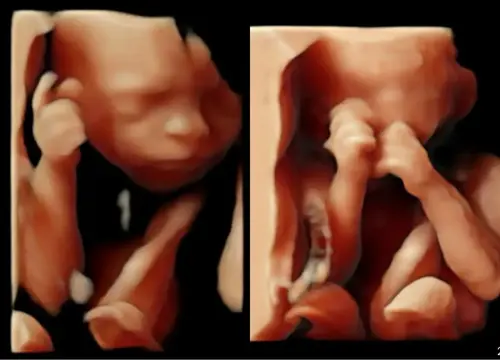

Ons menneke met 24 weken 💙

Wat een prachtig snoetje 😍